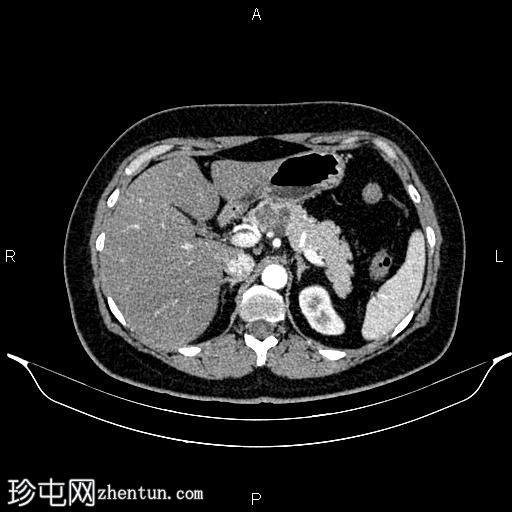

轴位增强扫描

动脉期

胰体近端可见一大小为32 × 27 mm的分叶状微囊性肿块,内部可见强化分隔,无明显钙化。胰腺其余部分未见异常,胰管未见扩张。

肝脏密度值低于脾脏,提示脂肪肝。